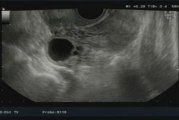

ROMA (ITALPRESS) -"La sindrome dell'ovaio policistico ha una forte base genetica che predispone ad alterazioni del metabolismo degli zuccheri e della produzione di ormoni maschili". Lo ha spiegato Alessandra Graziottin, professore a.c. Dipartimento ostetricia e ginecologia, in occasione della conferenza stampa dell'associazione Egoi per la Giornata Internazionale della Sindrome dell'Ovaio policistico. "C'è un malfunzionamento dell'ovaio - prosegue- per cui il ciclo è irregolare. La genetica predispone ma non è il destino, il nostro comportamento (soprattutto alimentazione e attività fisica), ci può aiutare a cambiare il destino". <br />xc3/mgg/gsl